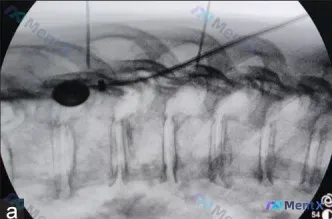

整理到一张脊柱微创介入的术中C臂透视影像(胸椎侧位),先不说结论,大家看看:

- 图像左侧可见一个椭圆形透亮区

- 有细长线性穿刺针/导丝影穿入目标椎体

- 目前未见明确的高密度骨水泥影

单从这一帧侧位片,你第一眼会往哪个方向想?